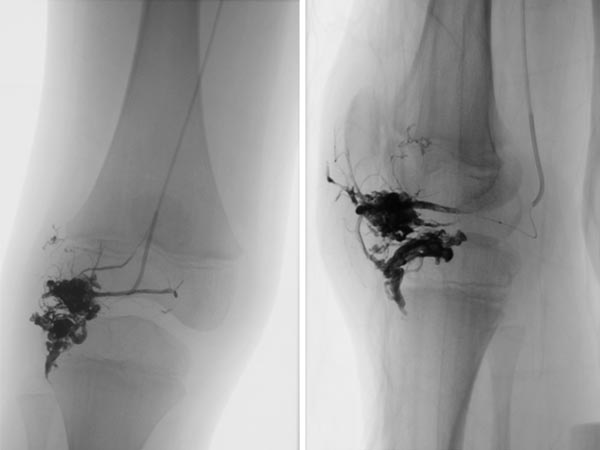

After renewed superselective catheterization of the AVM-feeding artery (lateral inferior genicular artery) ), the microcatheter is advanced to just before the nidus.

DSA image (roadmap technique) during re-embolization shows the freshly injected new additional embolic agent as black in the image.

Final DSA images (left AP, right lateral projection) after completion of repeat embolization again shows angiographically complete occlusion of both portions of the AVM.